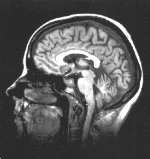

Após a invenção do tomógrafo computadorizado, vários métodos de produção de imagens foram desenvolvidos, como a MRI (tomografia de ressonância magnética), que produz cortes tomográficos a partir de campos magnéticos, a ultra-sonografia, e a cintilografia, com o uso de isótopos radioativos que além de gerar imagens de estruturas anatômicas, presta-se á avaliação da função orgânica; e entre as quais se conta o SPECT e o PET (tomógrafo de emissão positrônica).

Exemplos de processamento global de uma imagem de MRI. À direita: imagem borrada. No centro: imagem recuperada por processamento. ã direita: traçamento de bordas. Processamento realizado com o programa Adobe PhotoShop.